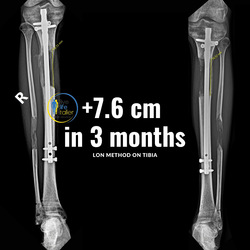

With the combined method (Lon method), an internal nail and an external fixation are attached which allow the bone to be extended from the outside.